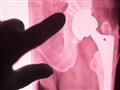

اتبعت هالة زريقات، رئيسة وحدة بحوث الهندسة الحيوية والأنسجة في كلية الهندسة بجامعة سيدني، نهجًا طبيًا جديدًا في عمليات العظام، يعتمد على زرع أجزاء سيراميكية ثلاثية الأبعاد تختفي تدريجيًا وتتحول مع مرور الوقت لعظام طبيعية، ما قد يقضي على الأساليب التقليدية المؤلمة فيما بعد، وفقًا لموقع «futurism».

تفاصيل الزرع

يحتوي الزرع على مكونات تشبه مكونات العظام الطبيعية، ولذلك استنتج الباحثون أنه قادر على الاختفاء بسلاسة دون ترك أي آثار جانبية سامة أو مخلوطة بالعظام، بالإضافة إلى احتوائه على مسامات تعمل كدعامة تستطيع العظام والأوعية الدموية أن تنمو من خلالها.

ويرفض جهاز مناعة المريض أحيانًا طرق ترقيع العظام المعروفة، عكس زرع السيراميك ما يجعله أداة مثالية تُستخدم لاستعادة العظام.

وتحتوي عملية الزرع على سيليكات الكالسيوم، وكميات صغيرة من السترونتيوم، والزنك، وهي من العناصر الشحيحة في العظام الطبيعية، وبالرغم أن العملية الجديدة قد تبدو قاسية، فإن استخدامها سيساعد كثير من الناس على تقليل الشعور بالألم والشفاء سريعًا.